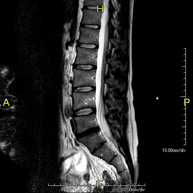

- RM Columna lumbar

Prueba diagnóstica no invasiva que consiste en la obtención de imágenes de alta definición anatómica de la lumbar y sacra, mediante el empleo de un campo electromagnético y ondas de radio (con un emisor y un receptor). No utiliza radiación ionizante. Indicaciones: traumatismos, ciática, hernias discales, tumores, infecciones.

Prueba diagnóstica no invasiva que consiste en la obtención de imágenes de alta definición anatómica de la lumbar y sacra mediante el empleo de un campo electromagnético y ondas de radio (con un emisor y un receptor). No utiliza radiación ionizante. Indicaciones: traumatismos, ciática, hernias discales, tumores, infecciones.